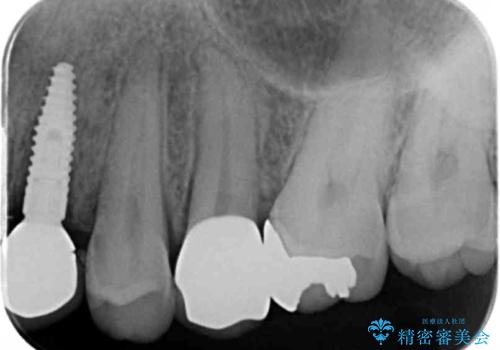

- ねじれてしまっている奥歯の矯正治療、銀歯のセラミック治療を求めて来院されました。

銀歯を外す前に部分矯正治療を行うことで歯のポジションを調整したのち、セラミック治療を行います。

90°ねじれてしまっていた歯を、矯正治療で治し、前後の歯の咬合関係も改善してしっかりと噛めるようになりました。